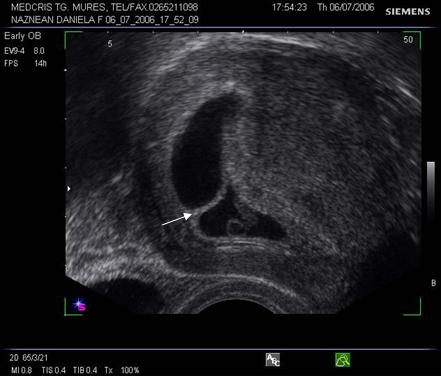

Fig nr 38. Sarcina biamniotica bichoriala 6 sapt . dupa

inseminare intrauterina cu stimulare ovariana, cele doua sageti marcheaza zona

de nidatie, respectiv placentatie, iar sacii amniotici sunt evident separati,

cu cate un embrion

Fig nr 39

Prezinta aceeasi sarcina biamniotica bichoriala,ca in figura precedenta, cu

semnul lambda marcat cu sageata